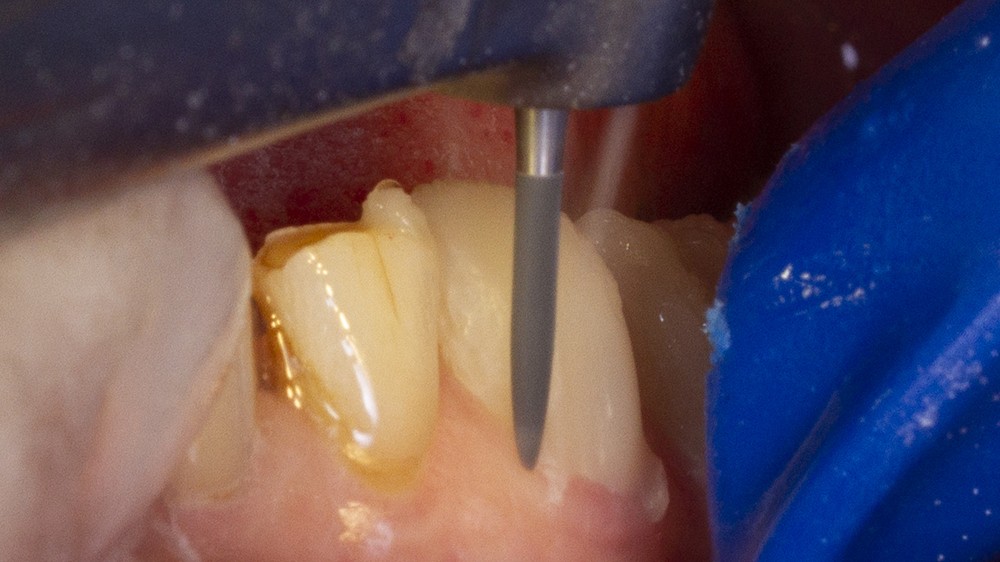

Le secteur incisivo-canin maxillaire débute la séquence thérapeutique selon la technique de pénétration contrôlée décrite par Galip Gurel [23].

Les restaurations postérieures bénéficient également de cette technique de préparation à pénétration contrôlée grâce à l’usage de fraises spécifiques. Elles s’effectuent à travers les composites collés. Ces derniers seront intégralement éliminés ainsi que toutes les anciennes restaurations sous-jacentes afin d’assurer un collage sur des tissus optimaux.